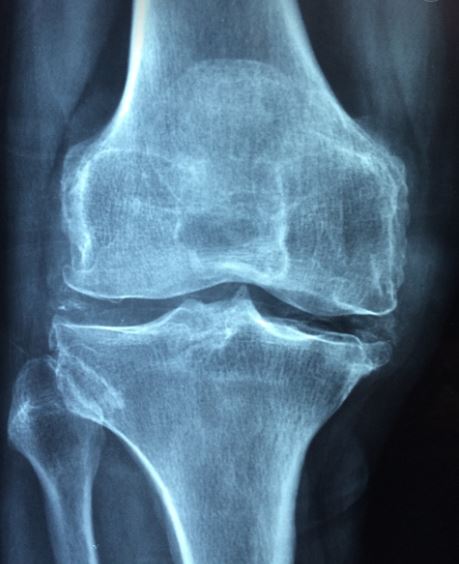

골다공증을 아시나요?

뼈의 주요 구성 성분인 칼슘이 빠져나가면서 골밀도가 낮아져

뼈가 약해지는 골다공증은 현대인들에게 너무 익숙한 질병중 하나 입니다.